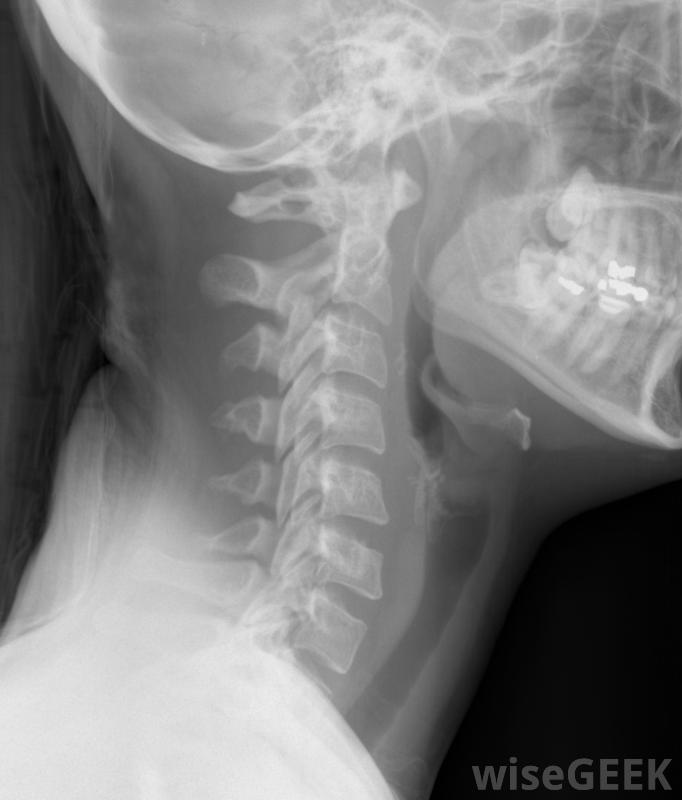

頸椎融合術采用植骨和器械相結合的方法,在上脊柱水平、咽喉和/或頸部創造額外的穩定性。它通常只是手術的一部分,盡管也可能有例外,并且往往伴隨著椎間盤切除術,或者椎間盤切除術。這種手術會導致一些小范圍的運動喪失,需要很長的恢復期,而且并不總是完全有效,很多病人都會因此感到舒服,恢復得很好。頸部X光片,包括頸椎通過頸部的前部或前部或后部,或頸部的后部進入脊柱。通常情況下,一個或多個椎間盤已被移除,開始進行頸椎融合術。這包括從人體供者處取骨,同種異體骨移植,或者直接從病人身上取下,自體移植到脊柱的空曠區域,用特殊的化學物質刺激其生長。視手術結果而定,許多頸椎融合術患者在幾天內就出院回家了。金屬或其他材料制成的器械也被固定在脊柱上以促進穩定性鋼板和大螺絲許多醫生認為這種器械的必要性有兩個原因:植入脊柱的小片骨頭需要幾個月的時間才能完全生長,并在脊柱水平之間形成骨性融合。另外,如果脊柱沒有融合,鋼板和螺釘將繼續為頸部提供穩定性患者在頸椎融合術后的幾周內都會戴上頸領,許多前路椎間盤切除和頸椎融合術的患者在幾天內就可以出院回家了。有些病人覺得困難的部分其實是從手術開始的。到第五到六周,大多數病人必須一直戴著硬領。大約在第四到第六周,患者也開始進行物理治療,以改善活動范圍,并對肌肉無力進行治療。當項圈最終脫落時,許多人可以重新開始工作,只要對身體要求不太高。椎間盤突出和壓迫部位可能是頸椎融合術的結果真正的頸椎融合術通常不會在6周內完成,盡管有些人可能已經開始融合。某些病人,特別是吸煙者,永遠無法實現融合,因為尼古丁會阻礙骨骼的生長。這可能會或可能不會引起并發癥頸椎融合術結合了植骨和器械,使脊柱上部更加穩定脊柱后凸,或脊柱前屈,頸部疼痛,或椎間盤摘除部位周圍出現新的椎間盤和壓迫問題。醫生有時建議再次手術以再次嘗試融合,這可能是僅有的一次融合不伴隨椎間盤切除術的情況。或者,建議手術治療頸椎的新問題,例如壓迫的神經或新的椎間盤。頸椎融合術后活動范圍的喪失取決于融合的脊柱節段的數目。單一節段不太可能導致明顯的損傷,但多層次融合可能會影響人們的轉頭能力。這是可以理解的,因為允許活動的彈性椎間盤已被骨取代。物理療法通常可以幫助人們彌補這些損失,但這需要時間盡管有可能的缺點,神經外科醫生和骨科醫生定期進行頸椎融合術,他們的病人往往報告積極的結果,大多數需要這種手術的人是在極端和無情的疼痛對于許多病人來說,放棄少量的頸部功能來達到緩解似乎是一種公平的權衡,當由稱職的外科醫生進行這項手術時,人們也被吸引到與此相關的高恢復率。